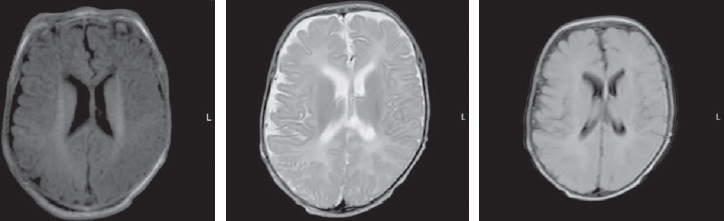

At the age of three months, an MRI of the brain revealed symptoms of delayed myelination, including an increase in the magnetic resonance signal of the posterior parts of the globus pallidus on both sides (Fig. 2).

Fig. 2. Magnetic resonance imaging of a patient at the age of 3 months. Axial sections, T1 VI, T2 VI, Flair. The signs of delayed myelination, were found to be symmetrical at the level of the perirolandic region. The architectonics of the furrows and convolutions have not been changed

Рис. 2. Магнитно-резонансная томограмма пациента в возрасте 3 мес. Аксиальные срезы, Т1ВИ, Т2 ВИ, Flair. Выявлены признаки задержки миелинизации, симметричные на уровне перироландической области. Архитектоника борозд и извилин не изменена